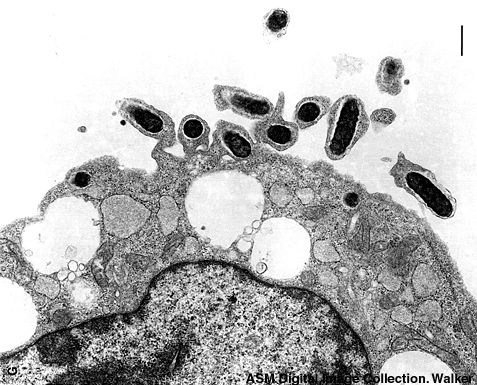

Rickettsias are among the smallest bacteria known, measuring ~ 0.3 - 0.5 um. They are obligate intracellular parasites (similar to chlamydia) in warm-blooded animals. Pathogens among these include R. rickettsii (Rocky Mountain Spotted Fever) and R. prowazekii (typhus fever). They are Gram-negative.